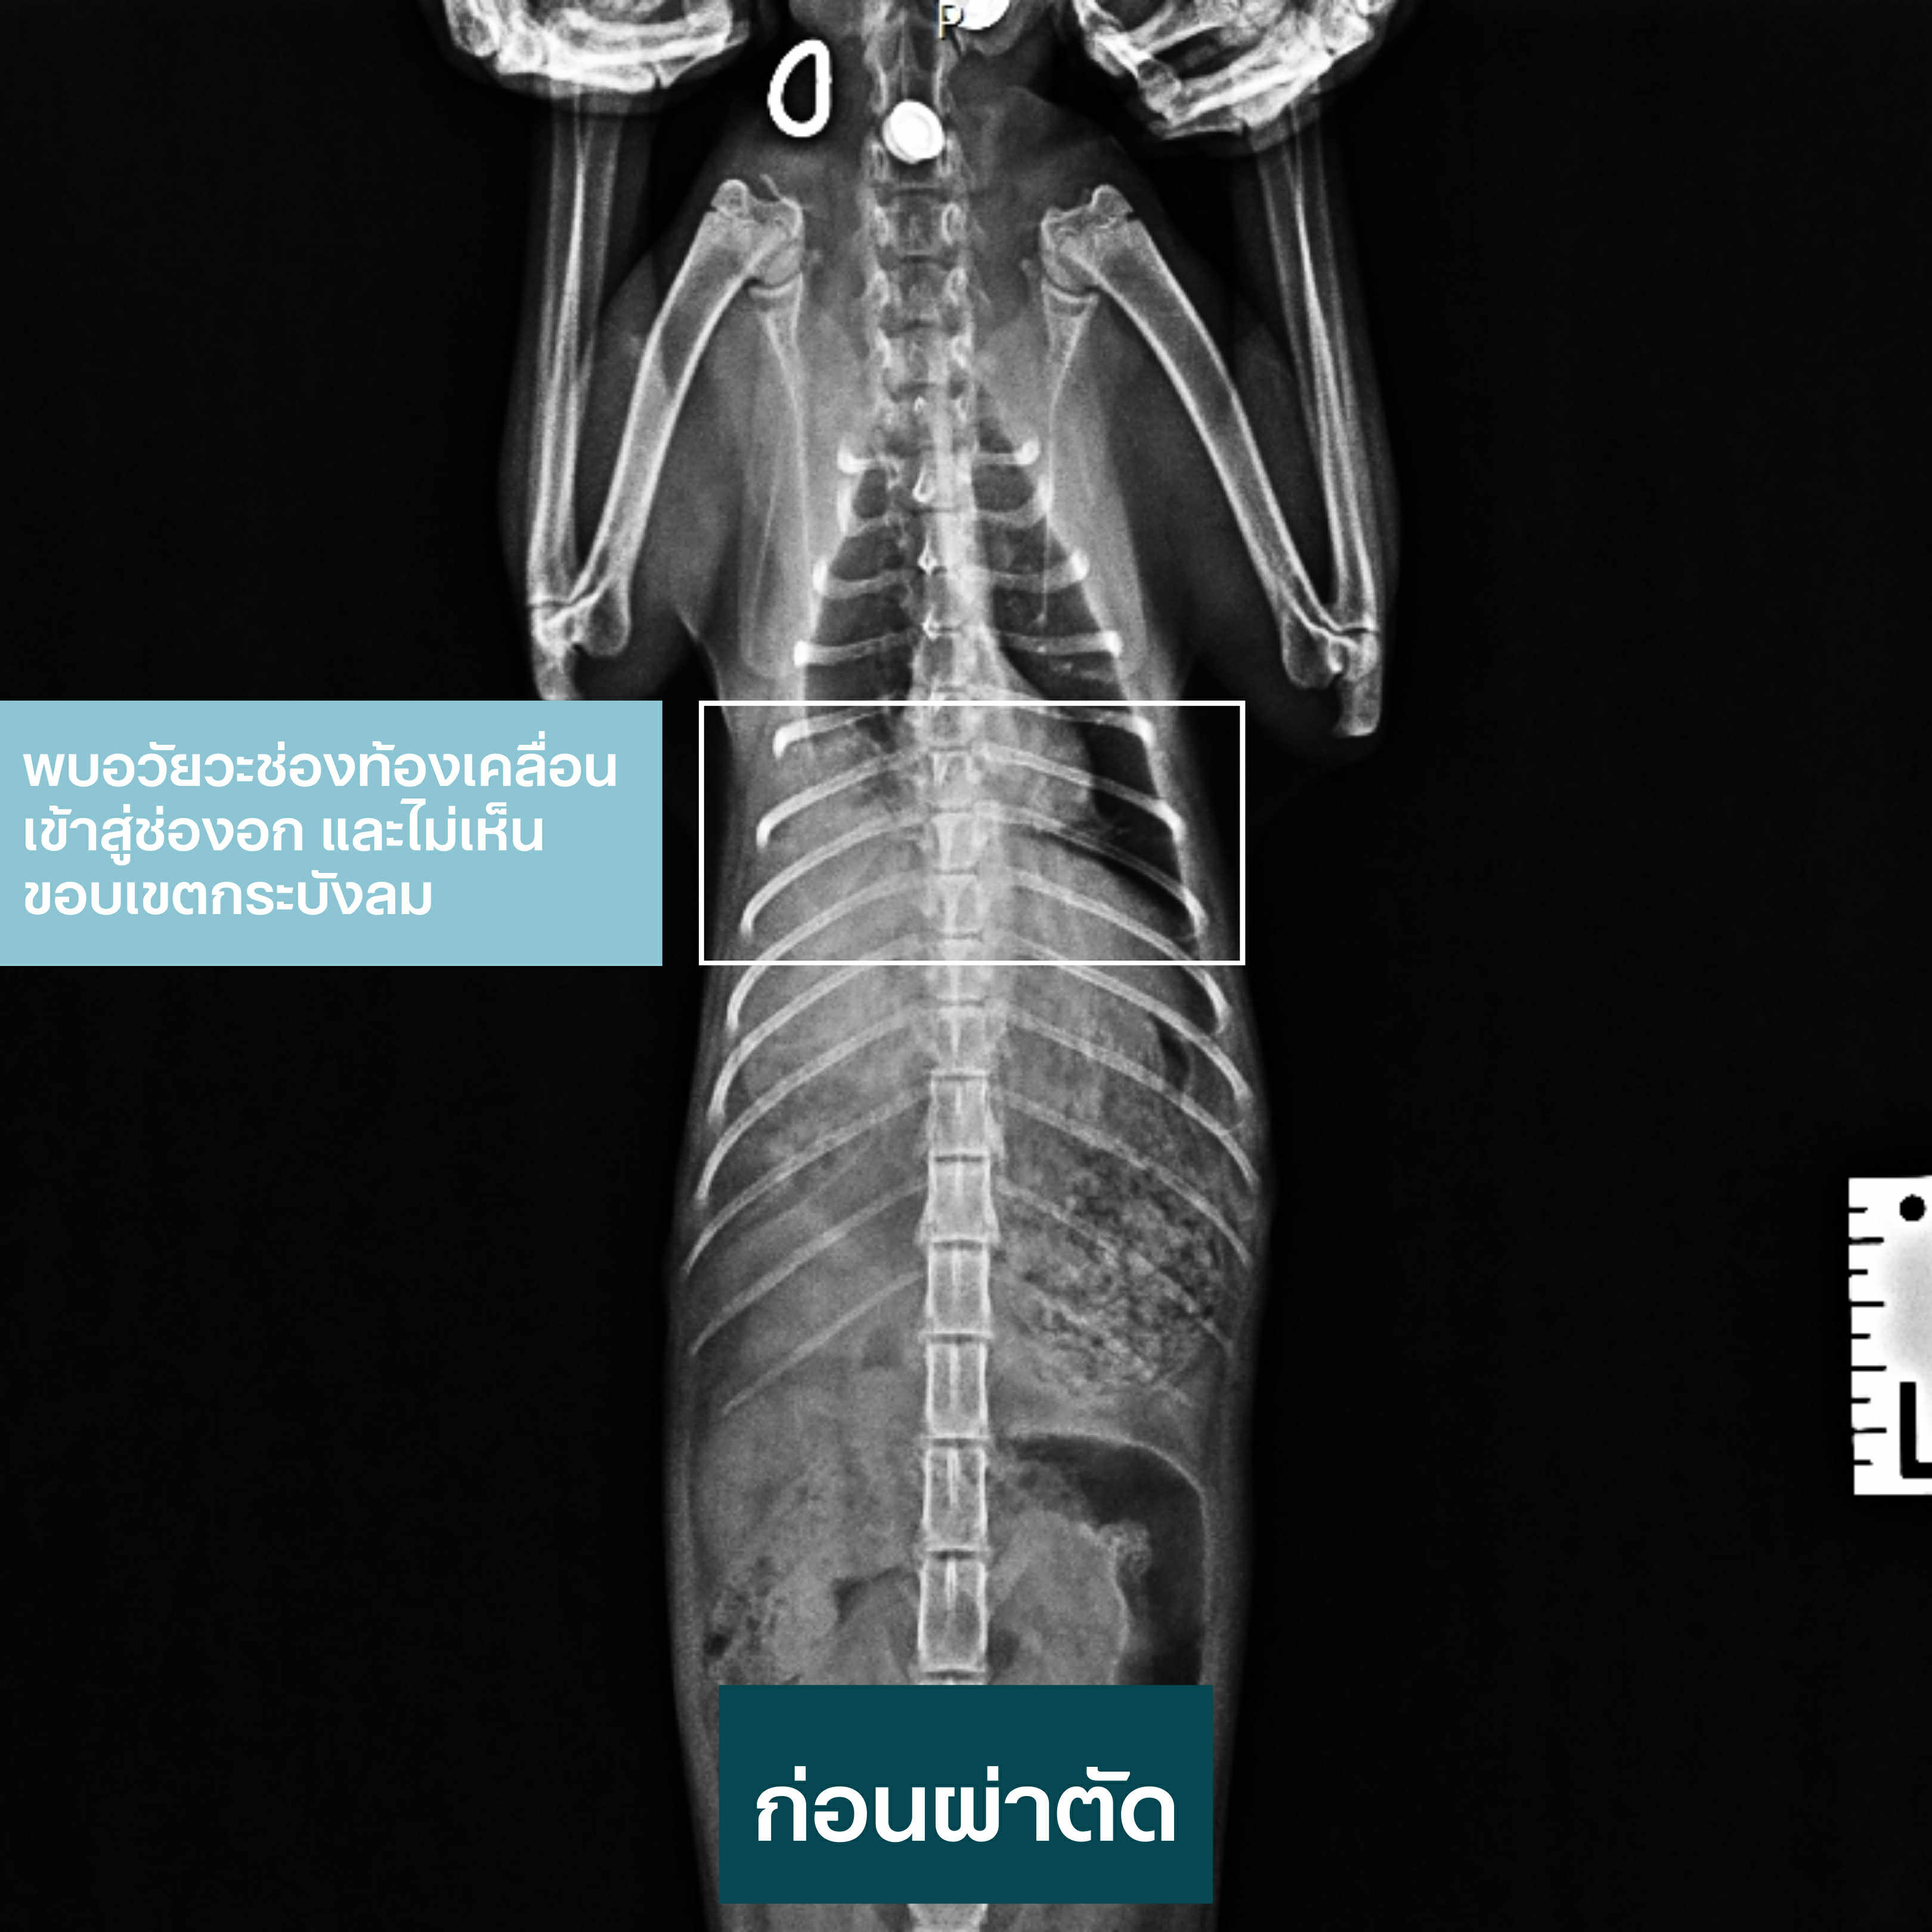

ก่อนผ่าตัด

X-ray พบอวัยวะช่องท้องเคลื่อนเข้าสู่ช่องอก และไม่เห็นขอบเขตกระบังลมชัดเจน